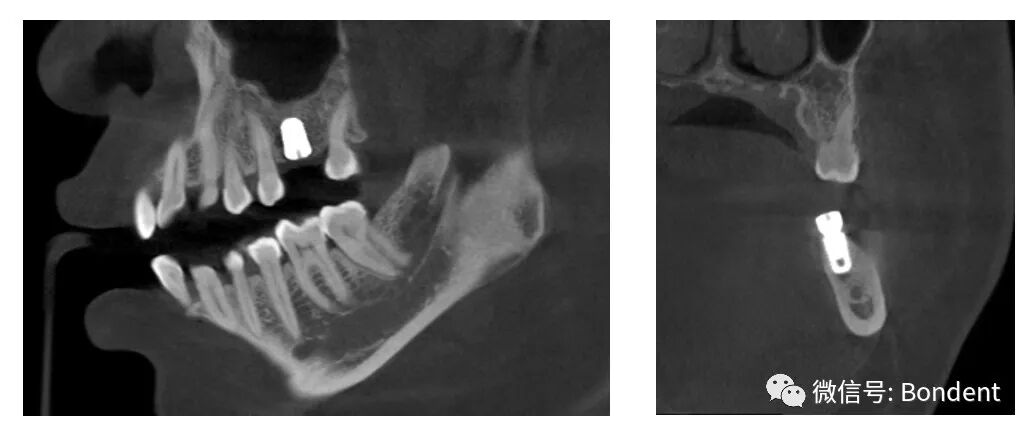

“伯爵Bondream”智能3D全景CBCT 多金屬去偽影圖

普通CBCT 多金屬去偽影圖(同一患者)

上頜竇底,骨小梁與下頜神經(jīng)管清晰可見(jiàn)

植體周圍無(wú)陰影,植體螺紋清晰可見(jiàn)

清晰的3D影像為實(shí)現(xiàn)數(shù)字化精準(zhǔn)治療保駕護(hù)航

OnDemand 3D后處理軟件直接模擬真實(shí)種植場(chǎng)景,更有骨密度精確測(cè)量,醫(yī)患溝通更直觀,手術(shù)更安全,患者更信任。